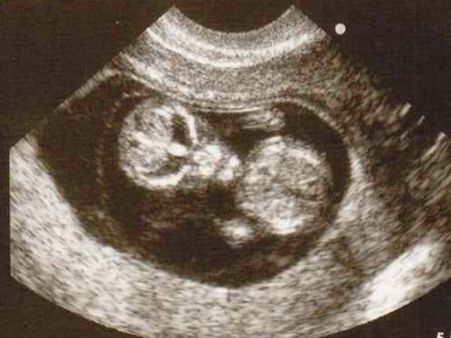

Picture# 1 The Alien Baby!

Does this child look exactly like an alien or is it a real alien baby? Well, the time would only reveal the real baby! We hope it comes in peace. Once the family realized the weirdness in the picture, it went viral!